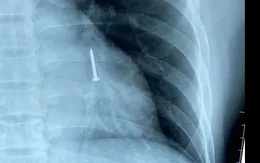

Nội soi gắp đinh sắt dài 3 cm trong phế quản bệnh nhân

VTV.vn - Ngậm đinh vào mồm để tiện đóng đinh cốp pha nhưng vô tình nói chuyện khiến nạn nhân bị hóc vào phổi. Sau 4 ngày không thấy đinh trong phân, nạn nhân vào viện cấp cứu...